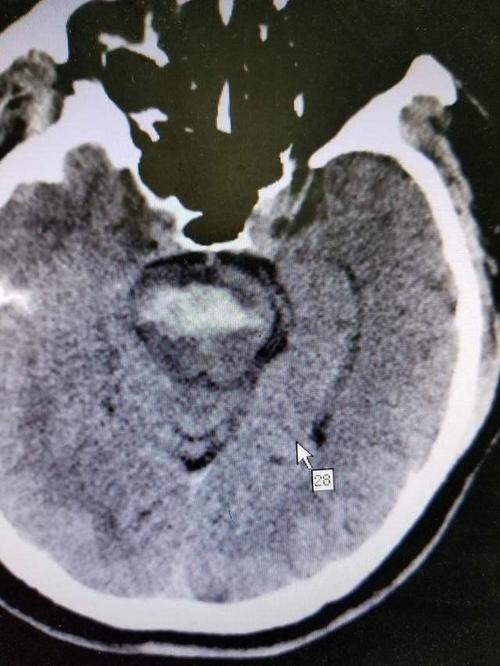

脑干变形 (Brain Stem Herniation/脑疝):

(图片来源网络,侵删)- 颅腔是一个坚硬的骨性盒子,没有多余的空间,当颅内压力过高时,大脑组织会被迫从压力高的区域向压力低的区域移位。

- 枕骨大孔疝:这是最危险、最常见的类型,由于小脑和脑幕下的压力极高,位于颅底最中央的脑干会被向下挤压,穿过枕骨大孔,进入椎管。

- 后果:脑干内部密集地分布着负责心跳、呼吸、血压等生命基本活动的神经核团,一旦脑干被挤压、变形、移位,这些生命中枢就会受到直接损伤或压迫,导致:

- 呼吸心跳停止:这是最直接的致命危险。

- 意识丧失加深:从嗜睡、昏迷到深昏迷。

- 瞳孔变化:一侧或双侧瞳孔散大,对光反射消失,是脑干受压的典型体征。

- 四肢去脑强直或去皮层强直:异常的肢体姿势,是脑干严重受损的表现。